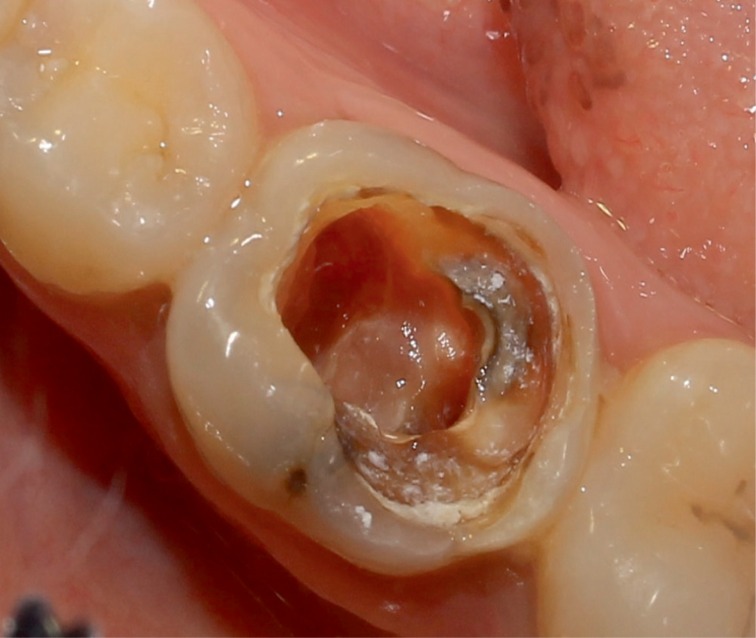

A 25 year old female patient presented to the Department of Conservative Dentistry and Endodontics with a chief complaint of pain in the region of the mandibular right first molar. She reported that an emergency access opening was performed one week prior for the same. Upon clinical examination, extensive destruction of the coronal tooth structure was noted (

Figure 1Preoperative photograph exhibiting extensive destruction of the coronal tooth structure.